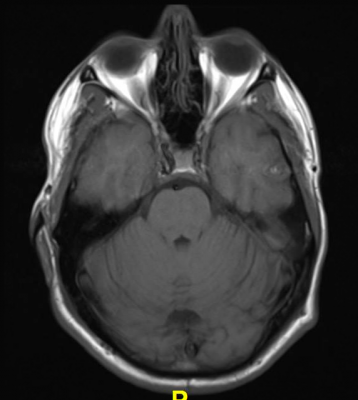

Acute Amnestic Syndrome Watch Out For Fornix Infarct To characterize mr signal changes associated with tissue damage in the fornix and cingulum in multiple sclerosis (ms) using quantitative mri measures and to determine associations with cognitive.